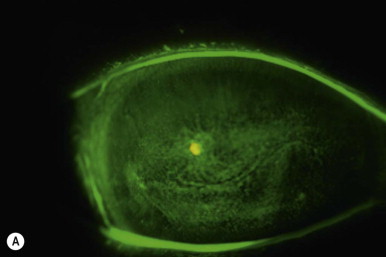

Eye suffering from Neurotrophic Keratitis

Prognostic indicators of this disease include the degree of sensory loss, length of time the condition existed, and the presence of other contributory ocular diseases (blepharitis, MGD, etc). Untreated ocular surface disease does worsen with time and the incidence of neurotrophic keratitis increases with age. Eye suffering from Persistant Epitherlial Defect